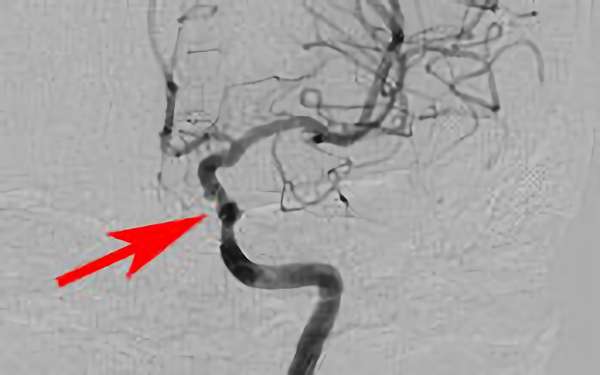

298

'18年11月13日

左内頚動脈狭窄症

60代

大阪府の病院